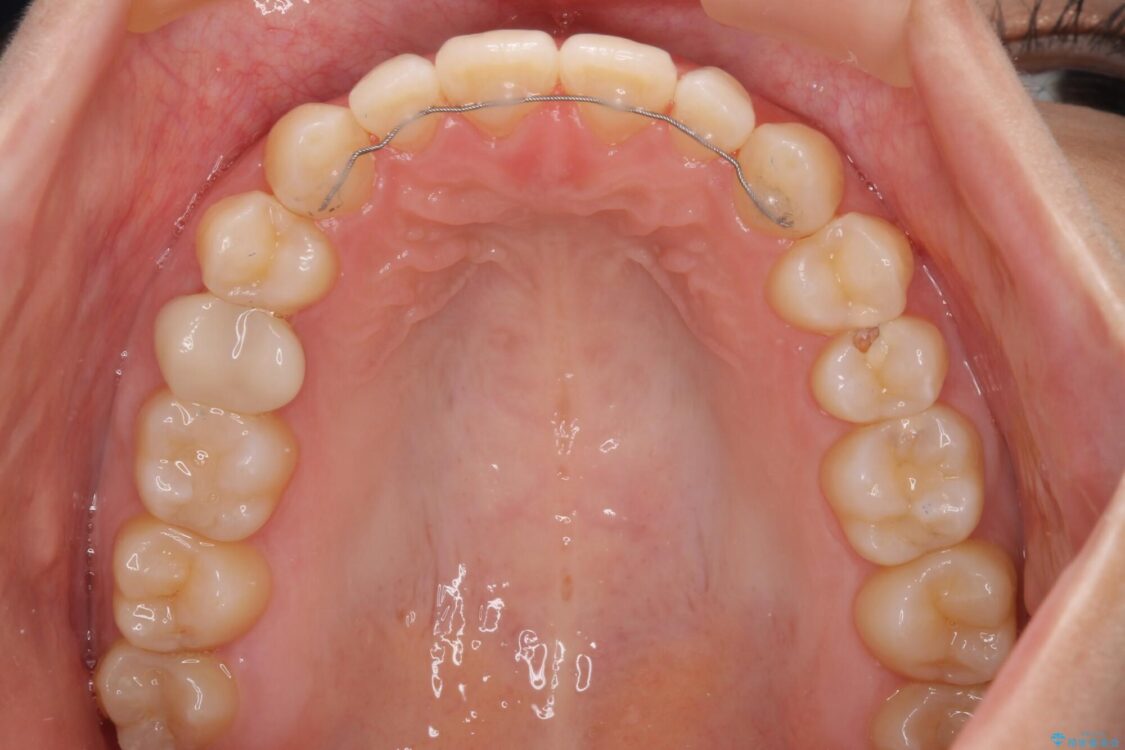

空隙歯列(すきっ歯)は、舌の突出癖をある程度改善できたとしても、後戻りにより隙間が開きやすいと言われています。

裏側から細いワイヤーで保定するとともに、睡眠時のマウスピース装着を徹底していただくことで、後戻りを最小限にとどめます。

治療後

• 隙間だらけの歯列 インビザラインで改善 治療後画像